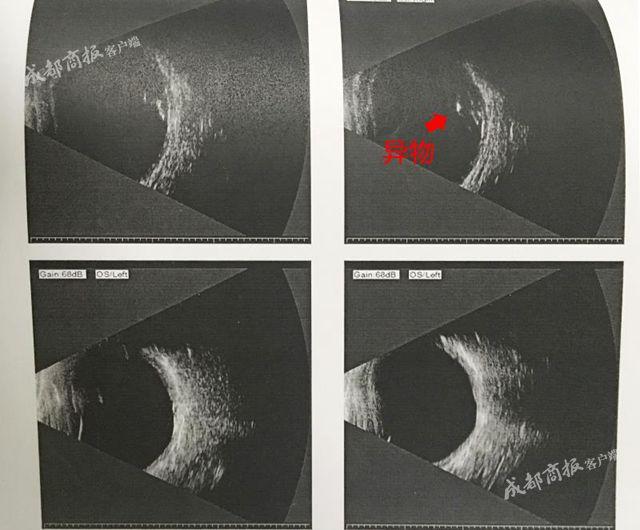

异物位置示意图

“我们检查发现,这个异物,在患者右眼后方。”周波说,异物是从章鹏右眼鼻侧斜着进入眼球,虽然击破了玻璃体,直击眼底,并在视网膜上形成了小孔。但万幸的是,异物避开了晶状体、角膜和眼底黄斑区。“黄斑区决定了能不能看清楚。”周波说,这是预后患者视力能够恢复的基础。

异物进入眼球的示意图